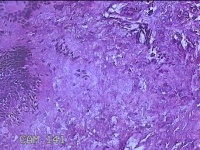

下唇肿物

性别

女

年龄

9岁

临床诊断

唇粘液囊肿

一般病史

下唇肿物1月

标本名称

大体所见

灰白暗红色肿物0.8x0.5x0.2cm一个,表面糜烂。